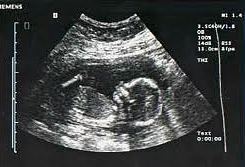

Stages of Fetal Development

3. Fetal Development

3. Fetal Development: